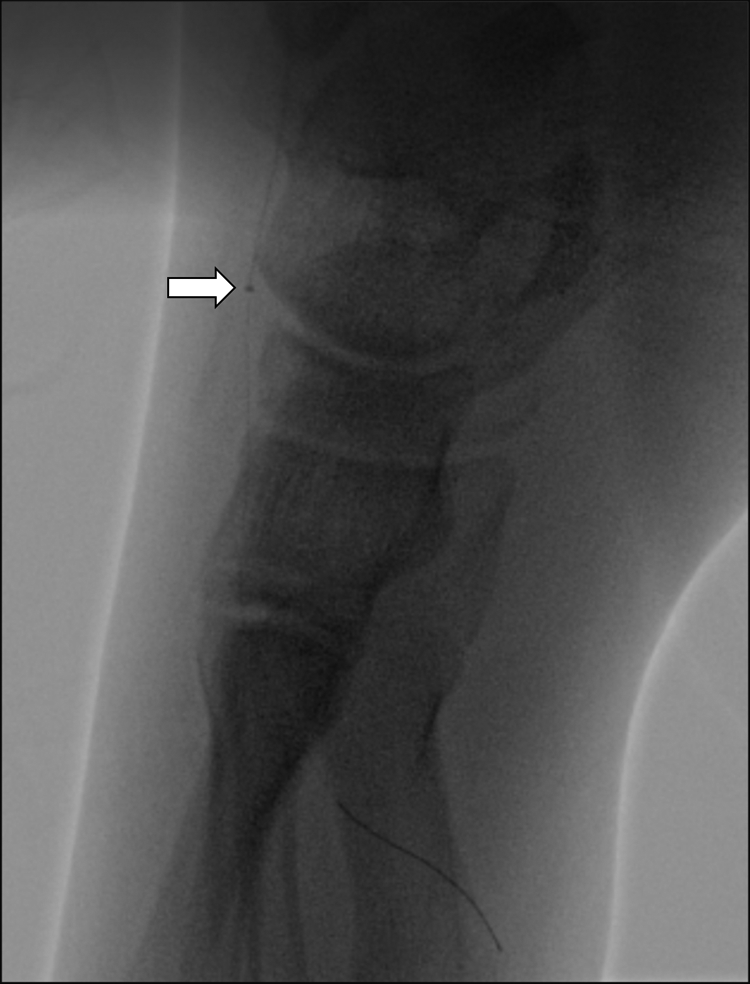

Figure 3

The Penumbra ACE 3Max aspiration catheter can be advanced into the left dorsalis pedis artery and pedal arch during aspiration thrombectomy (arrow). Small clots were retrieved.